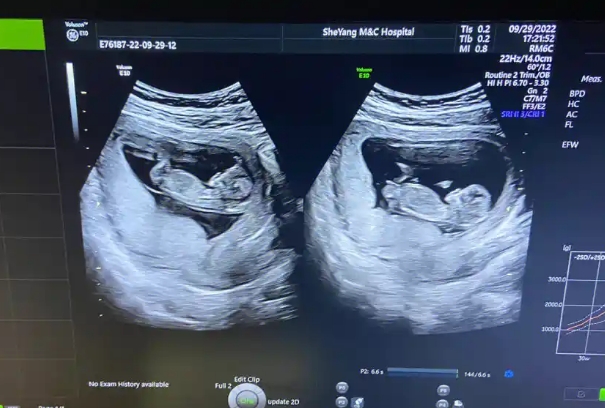

试管婴儿要做nt检查

为后续大排畸检查提供基线参考,早期发现异常可及时干预,评估多胎妊娠每个胎儿的发育状况

多胎妊娠:每个胎儿单独评估NT值